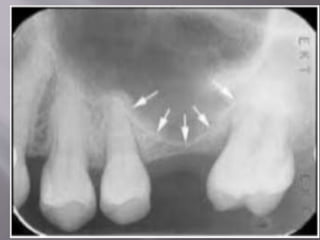

 Underwood's septa (or maxillary sinus septa,

singular septum) are fin-shaped projections

of bone that may exist in the maxillary sinus,

first described in 1910 by Arthur S.

Underwood, an anatomist.

 Based on origin they are of 2 types:

1) Primary septa: Formed during maxillary

development and tooth growth

2) Secondary septa: Acquired during

pneumatization of maxillary sinus after tooth

loss

 Location : most of the septa are located

between 2nd premolar and 1st molar region

 Origin : Arises from the medial and lateral wall

of sinus.

 Clinical importnace: septa makes sinus

augmentation processes difficult